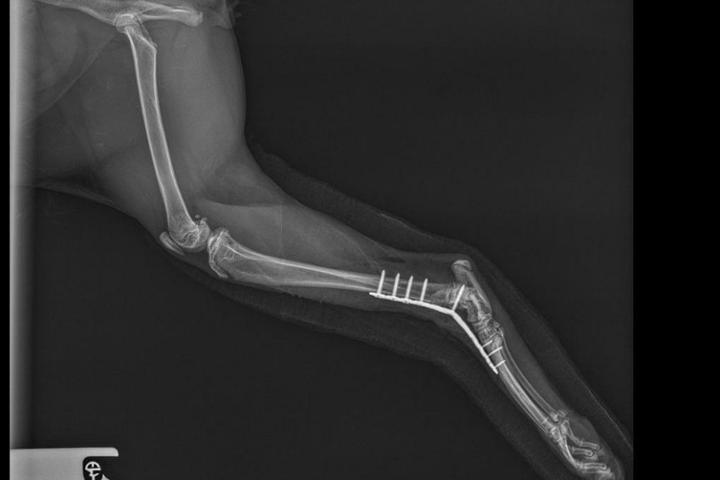

Andy, es un gatete que apareció en Chinchilla tras sufrir un atropello. La fractura que presentaba —tibia y peroné, muy cerca de la articulación— era especialmente complicada y requería una intervención con agujas y fijador externo. La buena noticia es que Andy ya ha sido operado, aunque durante la cirugía el equipo veterinario tuvo que adaptar el plan inicial debido a la cercanía de la fractura con la articulación. Aun así, la operación salió muy bien y ahora comienza su periodo de recuperación, que necesitará tiempo, tranquilidad y revisiones frecuentes. Gracias a vuestra aportación podremos cubrir: La cirugía y el material necesario (agujas, fijador externo). La medicación para el dolor y la inflamación. Las pruebas diagnósticas previas y posteriores. Las revisiones y curas durante su recuperación. 💛 Gracias por hacerlo posible. Cada euro suma y marca una diferencia real en la vida de gatos como Andy.